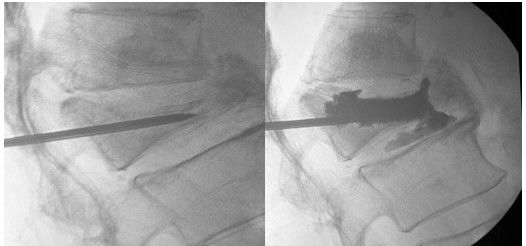

图注:左-脊柱压缩性骨折;右-注入骨水泥